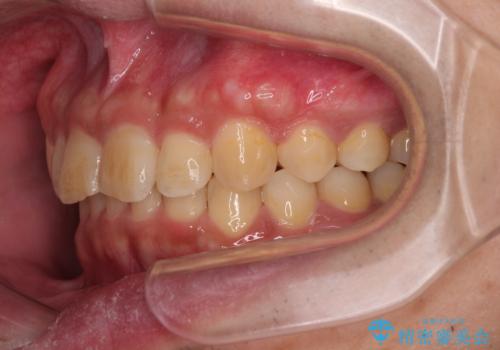

上顎歯列を遠心移動させたことで、前歯の叢生が解消されても前歯が前突することなく、左右ともに理想的な咬み合わせを達成することができました。